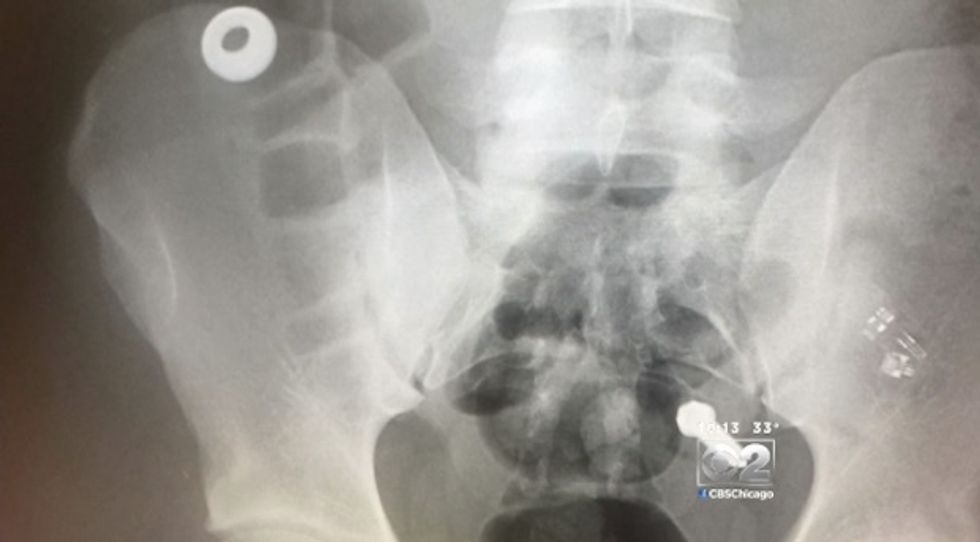

An investigation by WBBM-TV in Chicago has uncovered that some inmates held in Cook County Jail are actually eating parts of the jail. This very bizarre habit is also expensive, potentially costing the state of Illinois tens of millions of dollars in surgeries, aftercare and manpower costs.

Each case of an inmate ingesting pieces of metal means a trip out of the jail to a local hospital for evaluation, x-rays and possibly surgery. The costs are compounded because two guards must accompany each inmate.

According to the report, Lamont Cathey, is just one inmate with the metal-munching habit. Cathey has reportedly needed 19 to 20 surgeries, costing Illinois taxpayers more than $1 million.